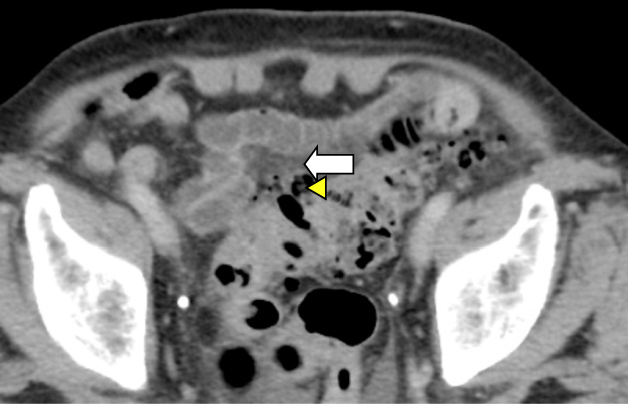

大腸憩室炎のCT画像

上行結腸憩室炎、Hinchey Stage I(a)、(a)の冠状断画像(b)

上行結腸憩室炎、Hinchey Stage I(c)、(c)の冠状断画像(d)

S状結腸憩室炎、Hinchey Stage III(e)、(e)の冠状断画像(f)

S状結腸憩室炎、Hinchey Stage II(g)、(g)の冠状断画像(h)